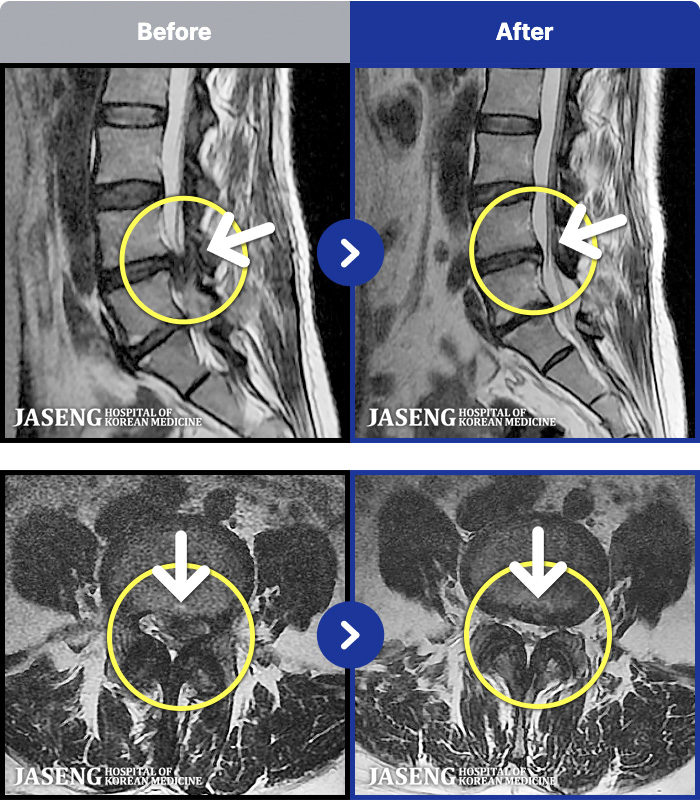

- MRI ġ

MRI ġ

1,301 MRI ũ ʸ Ȯϼ.